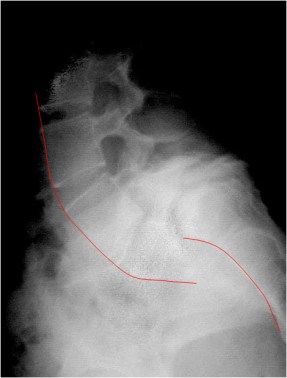

Aunque la radiografía lateral del mismo paciente no es muy buena, permite ver la marcada espondilolistesis L5-S1. La línea roja, que muestra los bordes anteriores de las vértebras lumbares y sacras, está claramente desalineada.